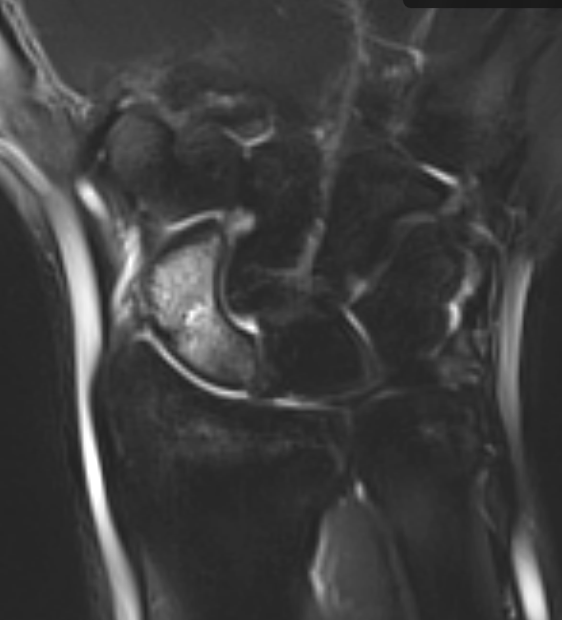

3. Scaphoid fracture